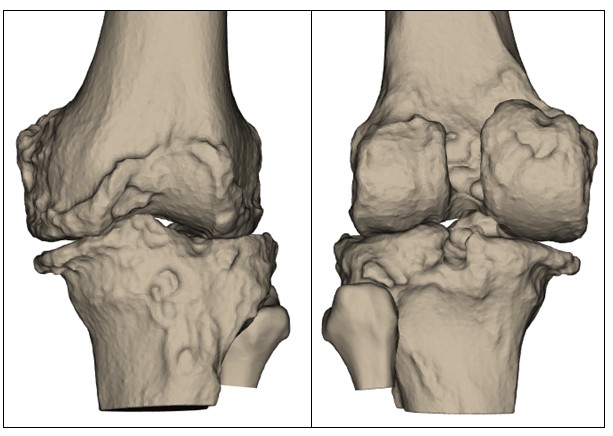

- Visible changes in your knee – Changes such as swelling, deformity (e.g. bow-legged or knock-kneed appearance), or a sensation that the knee is giving way or buckling under your weight can be signs of structural deterioration that may not be reversible without surgery.

- Advanced arthritis on imaging – If X-rays or other scans show significant damage caused by osteoarthritis, rheumatoid arthritis, or post-traumatic arthritis, knee replacement surgery may be the most reliable option to reduce pain and improve long-term joint function.

Before your surgery, your orthopaedic team will use detailed imaging, such as X-rays and a CT scan, to develop a personalised surgical plan. These scans provide an accurate 3D map of your knee joint, helping identify its shape, alignment, areas of cartilage loss, and how arthritis has affected joint movement. This information allows Prof. Justin Hunt or Prof. Vera Maria Sallen to plan your total knee replacement procedure with a high degree of precision. Key surgical decisions, such as where to make bone cuts, how much bone to remove, and how to position your implant, are made based on your unique anatomy.